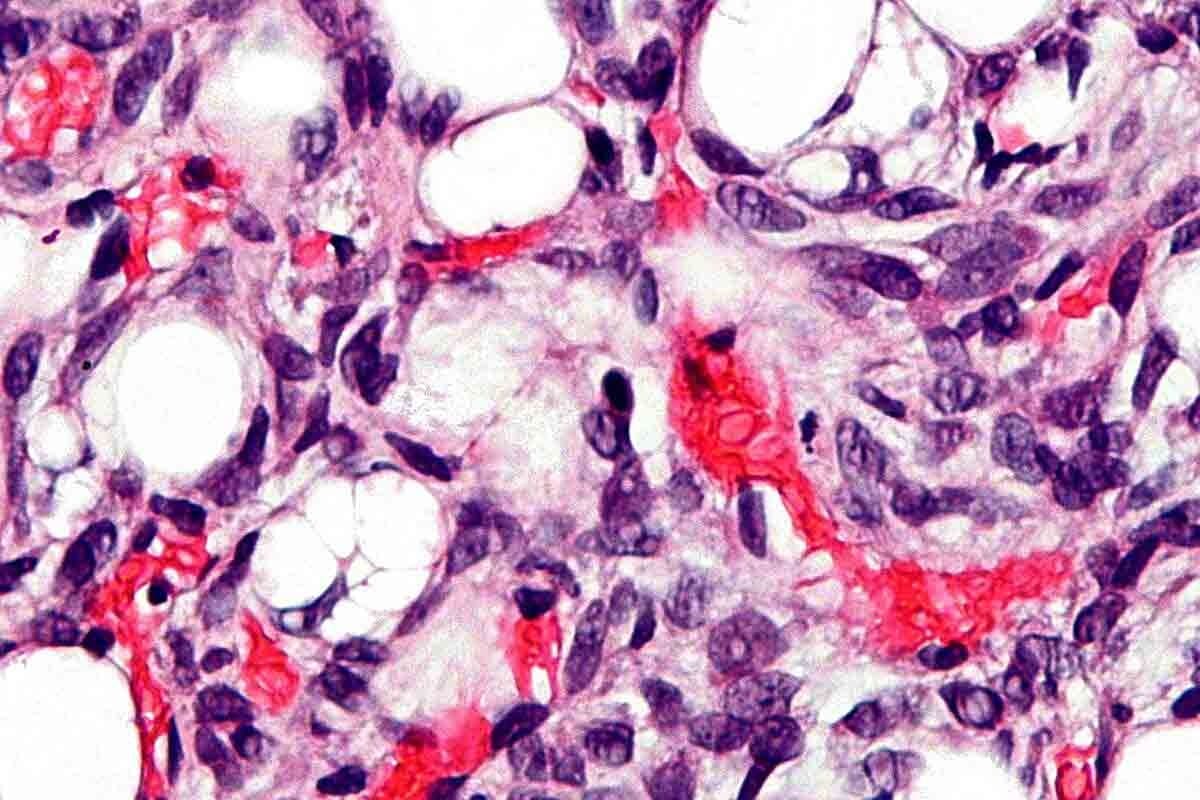

Tumor antigens are on cancer cells and can start an immune response. Immunotherapy vaccines target these antigens. This helps our immune system find and destroy cancer cells.

Cancer vaccines introduce tumor antigens to the body. This helps the immune system fight cancer cells better. We use different antigens and ways to deliver them to boost the immune response against cancer.

T-cells are key in how cancer vaccines work. They are a type of immune cell that can kill infected cells or start other immune responses. By making T-cells stronger, cancer vaccines help the body fight cancer cells better.